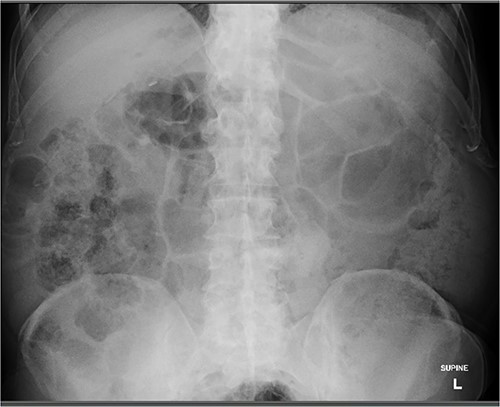

During the push enteroscopy the hearing aid could not be found despite thorough inspection of duodenal diverticula. The procedure was assisted by image intensifier guidance, and upon consultation with the onsite radiologist, the impression was that the hearing aid was in a jejunal diverticulum rather than a duodenal diverticulum. The procedure was abandoned and a single balloon assisted enteroscopy was planned for the following day. Prior to the procedure, the foreign body could not be located on the initial scout x-ray, and it was presumed to have passed naturally. Follow up formal x-rays again did not identify a foreign body (Figs 4 and 5), and the patient has been well since.